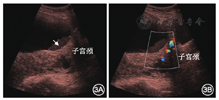

羊水内淤泥样沉积物(sludge)是指羊膜腔内的致密团状淤泥样、稍高回声沉积物,多近子宫颈内口或位于开放的子宫颈管内,可随孕妇体位改变而移动,见图3。Romero等[16]对羊水内淤泥样沉积物进行研究,抽出类"脓液"的物质,革兰染色显示其成分为上皮细胞、革兰阳性球菌及嗜中性粒细胞。淤泥样沉积物的出现与羊膜腔内感染有关。在无临床症状的孕妇中,羊水内淤泥样沉积物是出现足月前胎膜早破、自发性早产、羊膜腔微生物侵袭及组织学绒毛膜羊膜炎的独立风险因素[16,17,18]。除此之外,有学者持续观察胎儿肛门,可观察到胎儿排便,胎儿刚排出的胎粪可在羊水内形成淤泥样沉积物,一般呈不规则的稍高回声团,在胎儿肛门附近可观察到[6]。